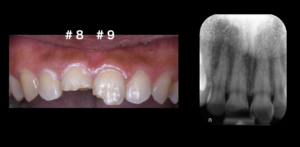

医院ブログ 2026/03/08

【表参道 歯科 ダイレクトボンディング】 破折した... こんにちは。表参道・青山にある歯科石上医院です。 自転車の交通事故…